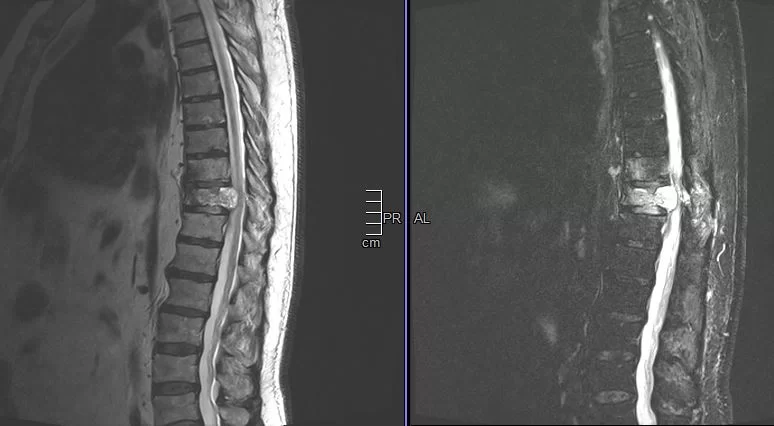

Παράδειγμα εξωσκληρίδιου όγκου: Ασθενής Άρρεν, 73 ετών, με γνωστή μεταστατική μάζα στον Θ10 σπόνδυλο, η οποίοα προκαλεί σημαντική στένωση του σπονδυλικού σωλήνα και πίεση επί του νωτιαίου μυελού. Διενεργήθη αποσυμπίεση του νωτιαίου μυελού και διαδερμική σπονδυλοδεσία/σπονδυλοπλαστική Θ9-Θ10. Μετεγχειρητικά ο ασθενής ανέφερε σημαντική πίεση του άλγους του και σημαντική βελτίωση της βάδισης.

(Προσωπικό Αρχείο Νευροχειρουργού Π. Σταυρινού)